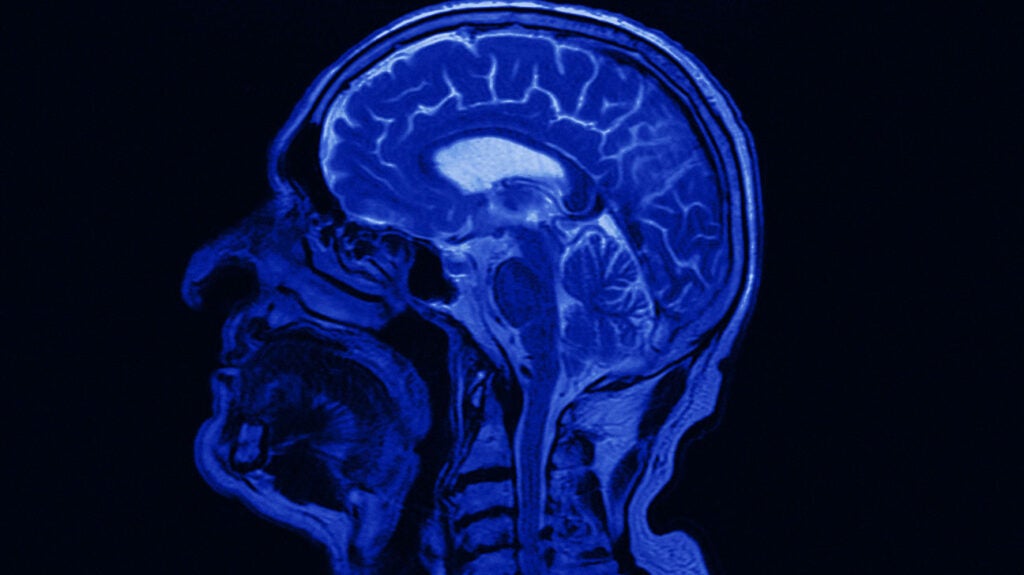

Pituitary adenoma MRI wikidoc Radiosurgery Pituitary Adenoma External beam radiation therapy (rt) has been demonstrated to be an effective treatment modality for pituitary adenoma, uncured by. Stereotactic radiosurgery (srs) and fractionated stereotactic rt (fsrt) provide high rates of tumour control i.e. Stable or decrease in tumour. Radiosurgery Pituitary Adenoma.